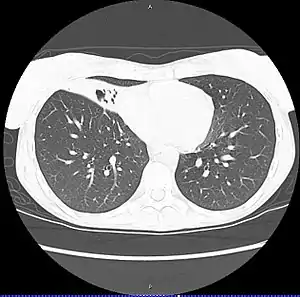

CT scan of patient with right middle lobe aspiration and Mycobacterium avium infection consistent with Lady Windermere syndrome

MAC usually affects patients with abnormal lungs or bronchi. However, Jerome Reich and Richard Johnson describe a series of six patients with MAC infection of the right middle lobe or lingula who did not have any predisposing lung disorders.[18][19]

The right middle lobe and lingula of the lungs are served by bronchi that are oriented downward when a person is in the upright position. As a result, these areas of the lung may be more dependent upon vigorous voluntary expectoration (cough) for clearance of bacteria and secretions.

Since the six patients in their retrospective case series were older females, Reich and Johnson proposed that patients without a vigorous cough may develop right middle lobe or left lingular infection with MAC. They proposed this syndrome be named Lady Windermere syndrome, after the character Lady Windermere in Oscar Wilde's play Lady Windermere's Fan. However, little research has confirmed this speculative cause.[20]